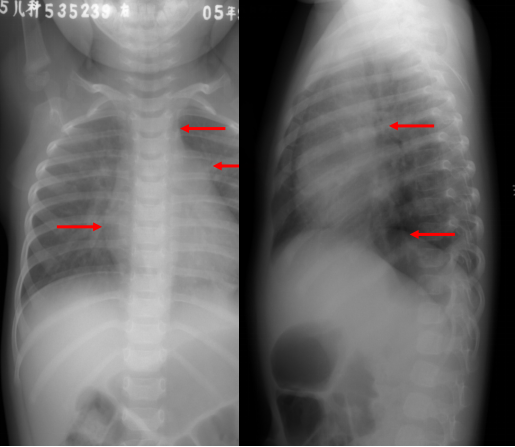

动脉导管未闭:胸片表现

◇ 肺血增多

◇ 心胸比例增大:>0.55

◇ 左房、左室增大

◇ 右室也可增大

◇ 肺动脉段突出

◇ 主动脉结不小或扩大